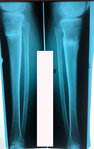

Дата операции - 24.10.2019г.

Дата снятия аппаратов - 22.01.2020

Срок сращения - 89 дней.